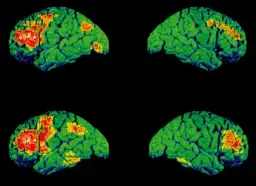

Dowiedz się, czy MRI głowy diagnozuje choroby psychiczne. Wyjaśniamy rolę rezonansu w psychiatrii, diagnostyce różnicowej i przyszłości leczenia.